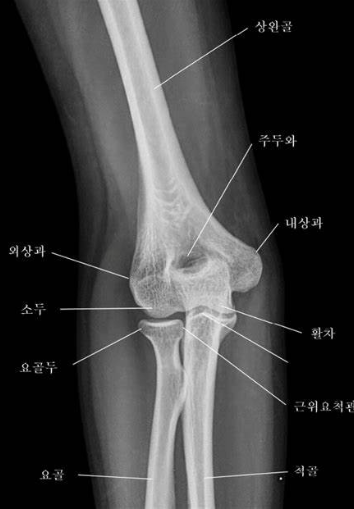

팔꿈치는 상완과 전완을 연결하는 복잡한 관절로 위팔의 상완골, 팔뚝의 척골 및 요골의 3개 뼈로 구성된 복잡한 경첩 관절로 우리 몸에서 중요한 역할을 합니다. 인대, 힘줄, 근육이 관절을 지지하여 다양한 움직임을 가능하게 하며, 일상생활의 다양한 활동에서 중요한 역할을 합니다.

팔꿈치의 해부학:Anatomy of the Elbow

팔꿈치 관절은 세 개의 주요 뼈로 구성되어 있습니다: 상완골 (upper arm bone), 요골 (forearm's radius bone), 그리고 척골 (forearm's ulna bone). 이 세 뼈는 팔꿈치의 기본적인 구조를 형성하며, 각각 다른 기능을 가지고 있습니다.

- 상완골 (Humerus): 상완골은 어깨와 팔꿈치 사이의 상완에 위치한 긴 뼈입니다. 이 뼈의 하단은 팔꿈치 관절의 일부를 형성하는 두 개의 돌출부, 즉 외측과 내측 상과돌기를 가지고 있습니다.

- 척골 (Ulna): 척골은 전완의 내측에 위치한 뼈로, 팔꿈치의 주된 힌지 기능을 담당합니다. 이 뼈의 상단에는 팔꿈치를 구성하는 중요한 구조인 척골 돌기가 있습니다.

- 요골 (Radius): 요골은 전완의 외측에 위치한 뼈로, 팔의 회전 운동을 가능하게 합니다. 요골 머리는 팔꿈치 관절 내에서 척골과 상호 작용합니다.